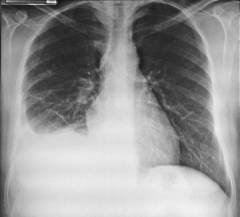

Рентгенологическое обследование — один из наиболее информативных методов, позволяющий выявить признаки воспаления и количество жидкости в плевральной полости.

Признаки при сухом плеврите на рентгене:

- купол диафрагмы с пораженной стороны выше нормы;

- снижение прозрачности легочной ткани.

Признаки при выпотном плеврите:

- сглаживание диафрагмального угла;

- однородное затемнение нижней области легочного поля;

- смещение средостения в сторону здорового легкого.

Рентгенологическое исследование — информативный метод диагностики плеврита, позволяющий выявить воспалительные процессы в плевре и оценить объем жидкости в плевральной полости. Рентгенография легких также помогает обнаружить заболевания, способствующие развитию плеврита, такие как пневмония, туберкулез и опухоли.

При сухом плеврите на рентгеновских снимках наблюдаются:

- купол диафрагмы с пораженной стороны выше обычного уровня;

- снижение прозрачности легочной ткани из-за воспаления серозной оболочки.

При выпотном плеврите фиксируются следующие рентгенологические признаки:

- сглаживание угла диафрагмы из-за накопления жидкости;

- однородное затемнение в нижней части легочного поля с наклонной границей;